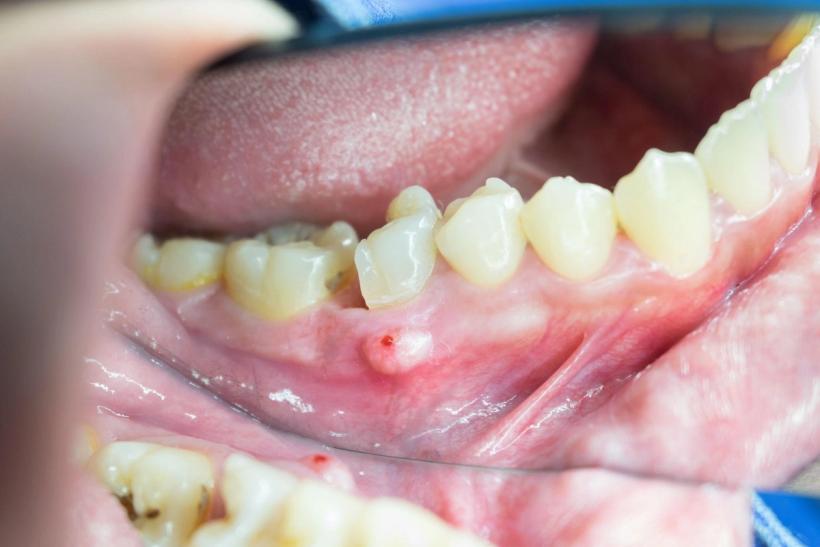

Swollen, red, or tender gums near the affected tooth

A visible bump (pus-filled swelling) on the gums, sometimes resembling a pimple